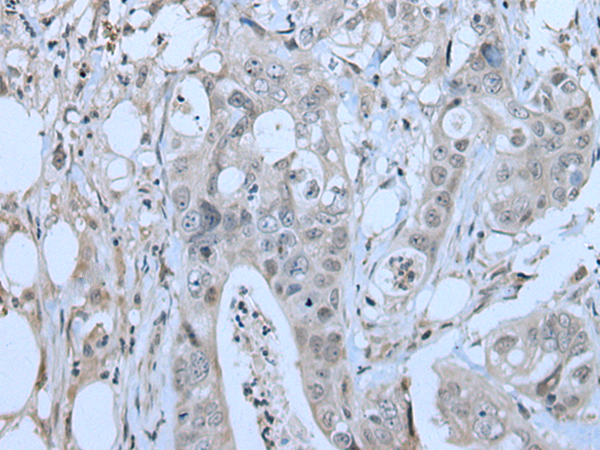

分类: 科研抗体货号: P12820别名: CENF; hcp-1; CILD31; PRO1779应用: IHC反应种属: Human

分类: 科研抗体货号: P12837别名: ZAP; ZC3H2; ARTD13; PARP13; FLB6421; ZC3HDC2应用: IHC反应种属: Human

分类: 科研抗体货号: P12836别名: C19orf7应用: IHC反应种属: Human, Mouse

分类: 科研抗体货号: P12818别名: ATG1; ATG1A; UNC51; hATG1; Unc51.1应用: IHC反应种属: Human

分类: 科研抗体货号: P12835别名: ZNF923应用: IHC反应种属: Human